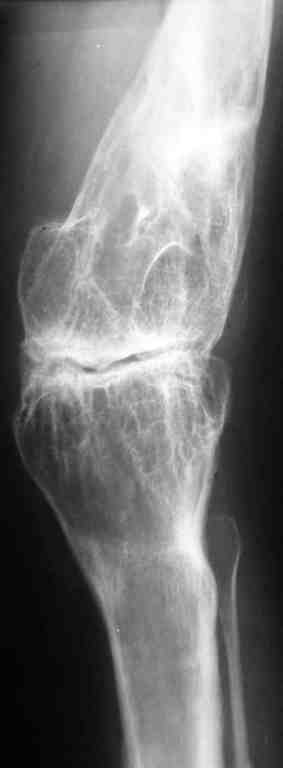

Уважаемые коллеги! К мне обратилась моя бывшая пациентка, 22 лет, с просьбой об

эндопротезировнии коленного сустава. От артродеза категорически отказывается.DS:

Врождённая аномалия развития левой нижней конечности. Состояние после удлинения бедра и

голени (около 45 см). Варусная деформация шейки лев. бедра. Лев. коксартроз II ст. Лев.

гонартроз III ст. Разгибательная контрактура лев. коленного сустава. Парез малоберцового

нерва слева. Укорочение лев. н/конечности 1,5 см.

Жалобы: на боли и нарушение функции в лев. коленном суставе. St. locales: ходит в брейсе с

опорой на 1 трость. Относительная длина ног S 1,5 см. Движения в лев. т/б суставе: сгиб. 70 ,

разг. 180 , привед. 60 , отвед. 110 , вн. рот. 20 , нар. рот. 10 ; в лев. к/сус. пассивно: сгибание 0

, разг. - 180 + 30 ; активно на переразгибание и из положения переразгибание на сгибание

2балла. Под нагрузкой вальгусно-рекурвационная деформация: клиничски на val. 15-20 , rec.

- 30 . Движения в лев. голеностопном суставе (акт./пас.): тыл. фл. 0 /90 , под. фл. 170 , отвед.

10 /15 , прив. 25 . Функция в других суставах не нарушена. Предполагаю, что наиболее лучшим

вариантом будет двух этапное протезирование. На первом этапе устранить антекурвацию на

бедре аппаратом Илизарова; вторым этапом протезирование заднее-стабилизирующим

протезом фирмы "Zimmer" , т.к. маленькие размеры бедренной и большеберцовой костей.

Возможны ли другие варианты лечения? Возможно ли одно этапное

протезирование?

Целесообразно ли в данном случае протезирование? Может быть не стоит